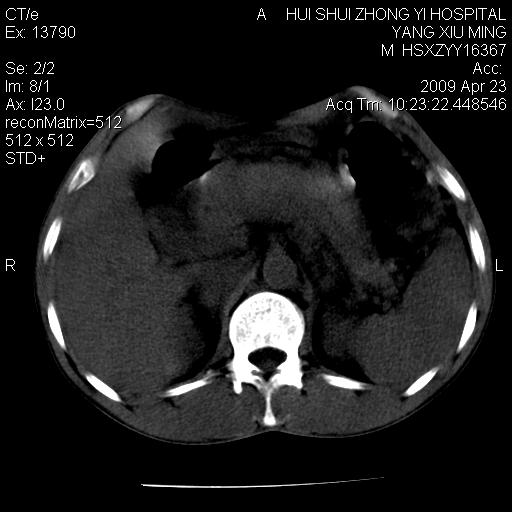

上腹部疼痛一月,呕吐10天,发现左侧颈部包快10天 胸部cr片未见明显异常。

腹膜后淋巴结增大,转移、淋巴瘤?胰腺增大,胰腺炎?占位?颈部考虑增大淋巴结。建议腹部增强扫描。

缺少强化资料,暂考虑胰腺癌广泛转移.

黑!广泛淋巴结肿大不符合胰腺癌转移。胰腺周围淋巴结肿大致使胰腺看起来大。考虑淋巴瘤可能大。